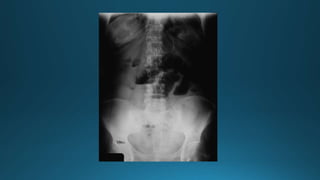

• 22.

Diagnóstico Íleo paralítico oadinámico Estudio de imágenes Radiografías Radiografía Simple de abdomen -Dilataciónde las asas afecte o pueda afectar a todo el intestino. -La presencia de niveles hidroaéreos hace difícil su diferenciación de el íleo mecánico